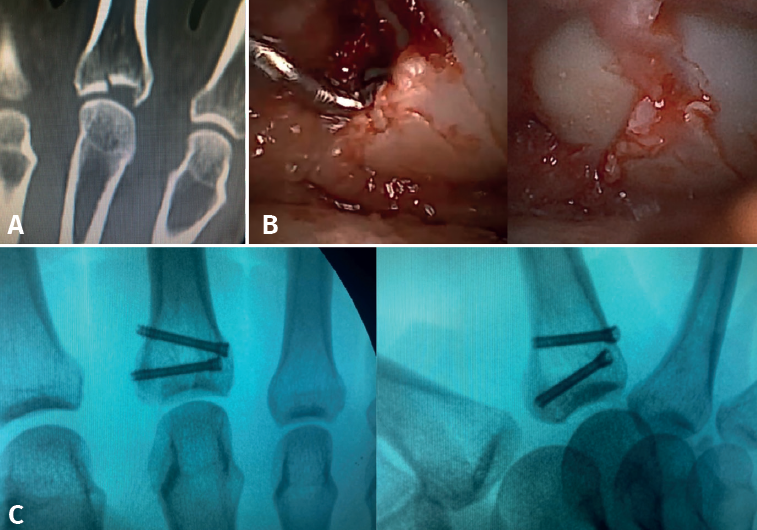

- Intra-articular fractures proper, caused by compression or shear mechanisms.

Metacarpal head fractures, although less common, are also amenable to treatment by this method, particularly if comminution is present(1).

Arthroscopy allows removal of any osteochondral fragments, anatomical reduction of the main fragments, synovectomy, and removal of the intra-articular hematoma, as well as (according to some authors), thermal capsular contracture to help reduce the inflammatory process(1).

The main fragments are reduced with the aid of a palpator or a small blunt dissector. External reduction of the fragments may be necessary, especially when they are impacted in the centre of the articular surface. This is especially common at the base of the proximal phalanx. To do this, we introduce a 1.0 Kirschner wire through the fracture site, through an extra-articular "window", and in "joystick" fashion, we lower the impacted fragment. Sometimes it is advisable to check each of the maneuvers using fluoroscopy, which can be positioned perpendicular to the arm or in the traditional manner, which requires us to release the hand of the patient in order to perform the check.

Once the fragments have been reduced, 0.8 or 1.0 Kirschner wires are used to maintain reduction (Figure 7). Sometimes we can only maintain reduction by applying a stop, to prevent the osteochondral fragment from collapsing. Depending on the fracture pattern and the surgeon's preference, we can use conventional screws, cannulated screws, etc. (Figures 8 and 9).